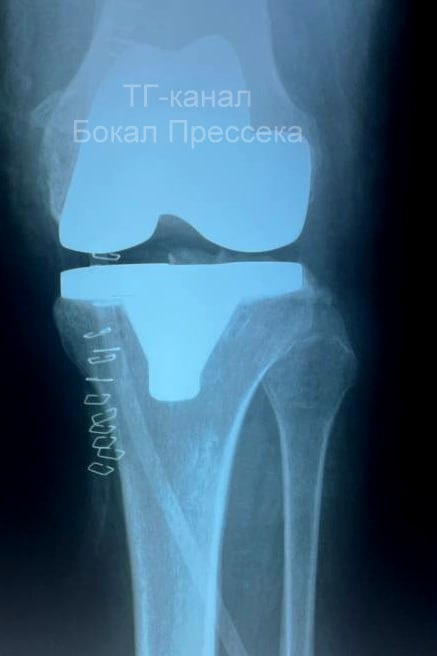

Нижегородке с экстремально большим весом заменили коленный сустав

Нижегородские врачи прооперировали 56-летнюю женщину, которая весить более 120 килограммов. Ей заменили коленный сустав. Об этом представитель сферы здравоохранения Алексей Никонов сообщил в Тelegram.

Он пояснил, что обычно пациентам с таким экстремально большим весом операции не делаются. Но женщина с разрушенным коленным суставом испытывала невыносимые боли, ей было невозможно ходить. Травматологи больницы № 13 пошли на риск и решились на операцию.

Вмешательство прошло успешно, пациентке установили имплант из спецмедсплава кобальта, хрома и молибдена. Женщина ужеможет передвигаться с помощью ходунков, но врачи настоятельно рекомендуют ей похудеть хотя бы на 10–15 килограммов. Это существенно продлит срок службы импланта.